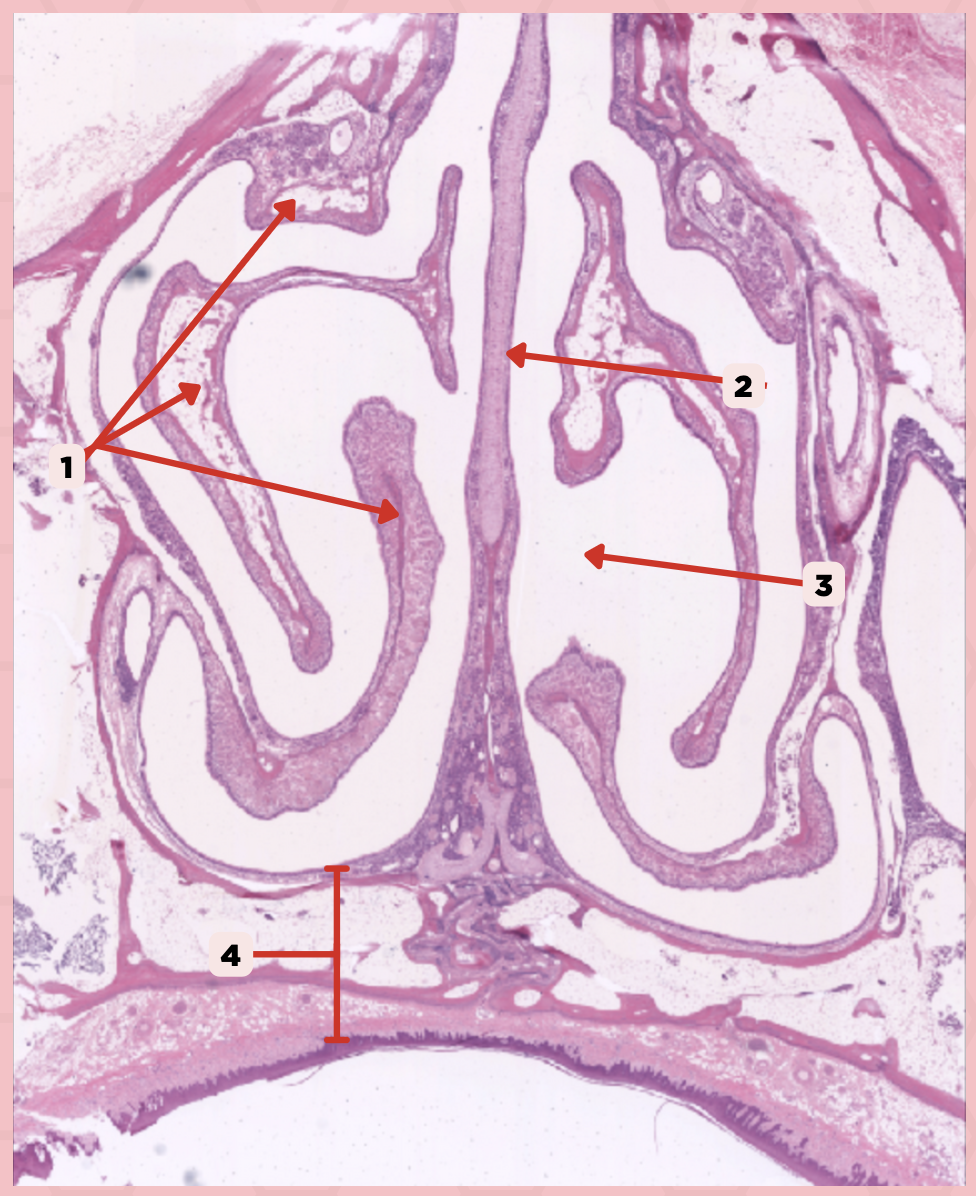

Nasal Cavity

What are the spaces found immediately lateral to #2?

Nasal Turbinates (conchae)

Identify the structure labeled as 1.

Nasal septum

Identify the structure labeled as 2.

Nasal cavity

Identify the structure labeled as 3.

Hard palate

Identify the structure labeled as 4.

Mucosal Associated Lymphoid Tissue (MALT)

What time of lymphocyte is numerous in the nasal cavity?